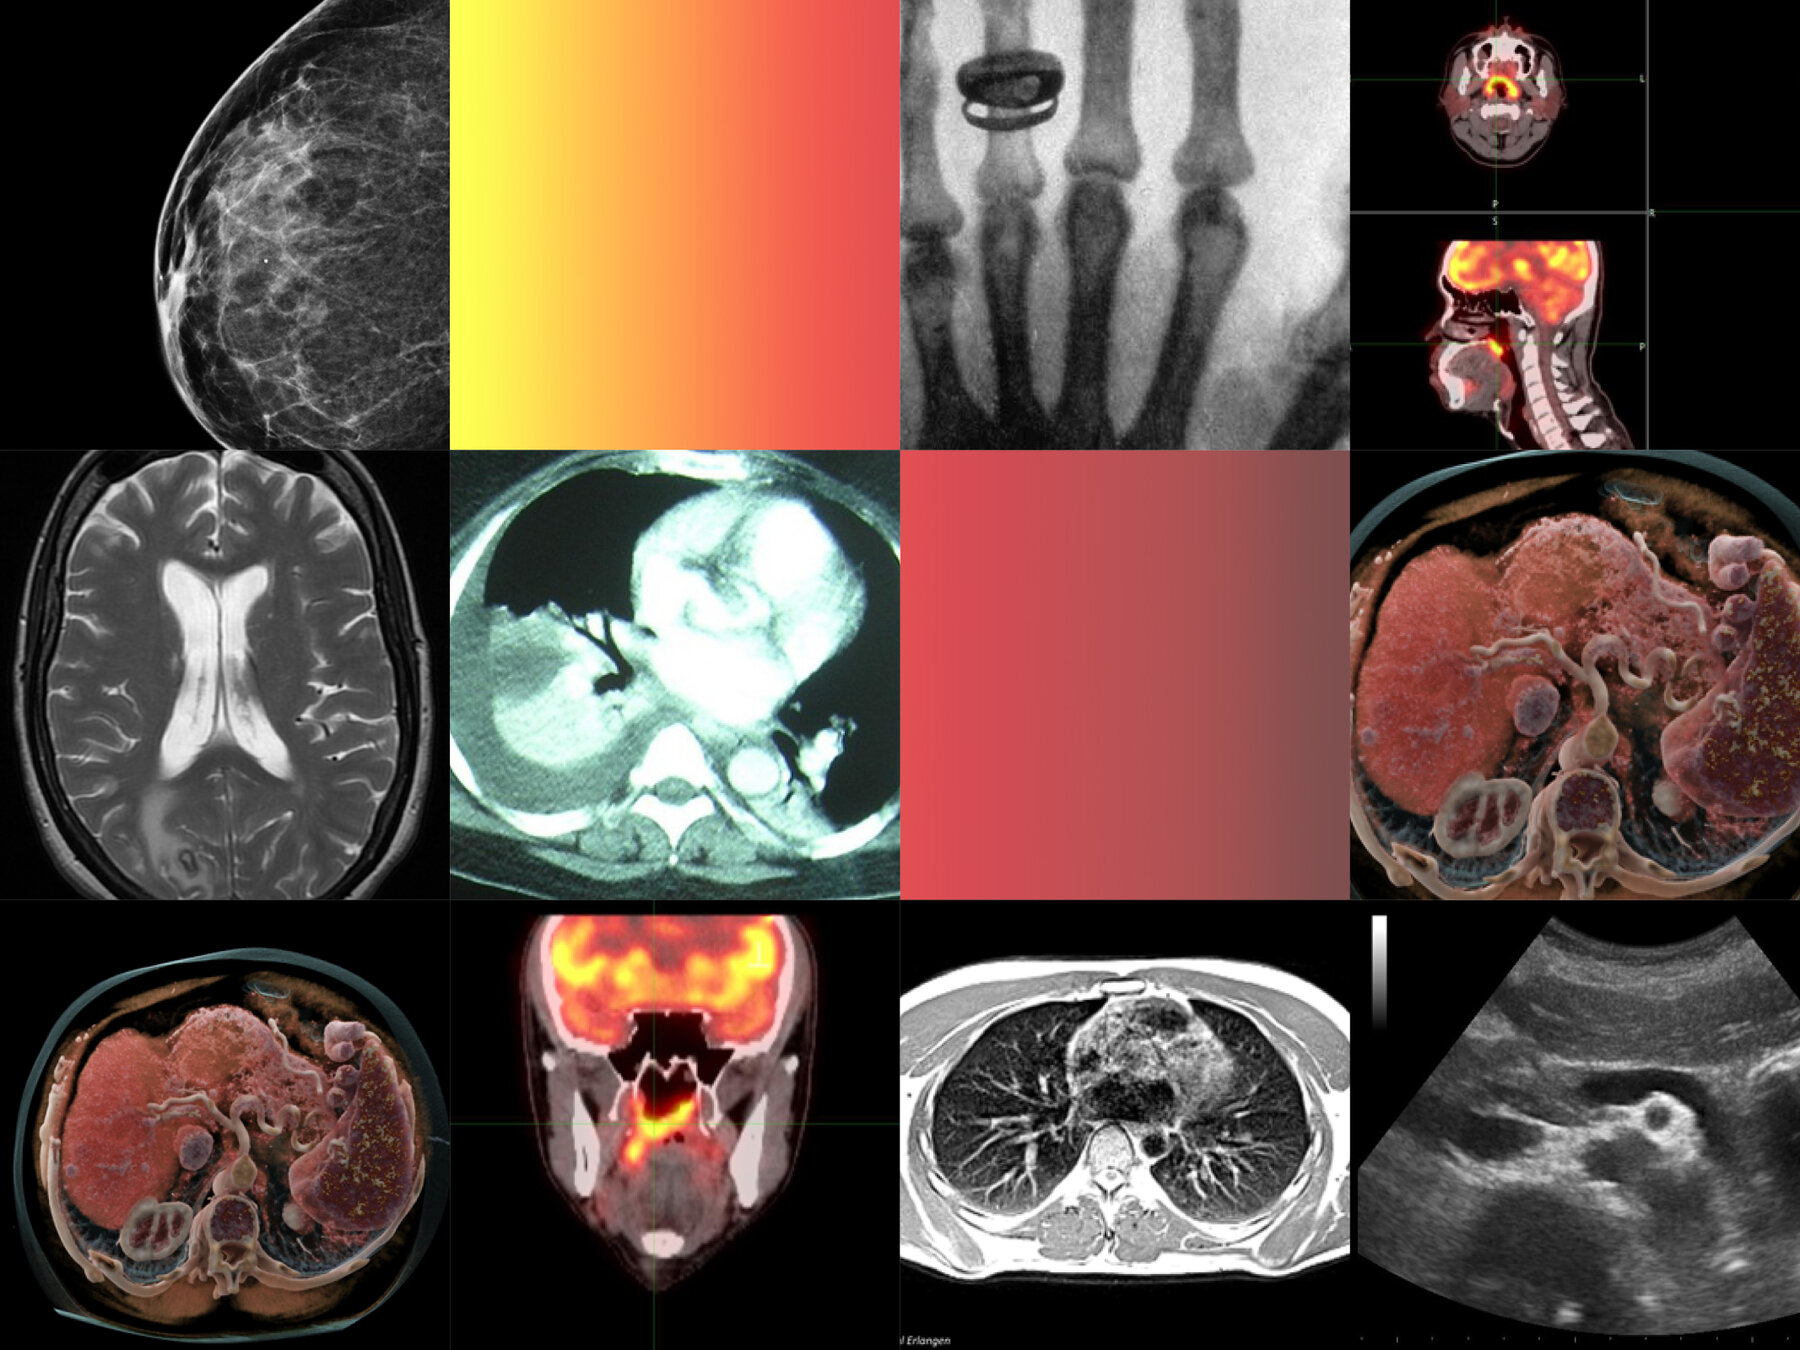

principalmente basadas en imágenes médicas

- Introducción al procesamiento de imágenes médicas.